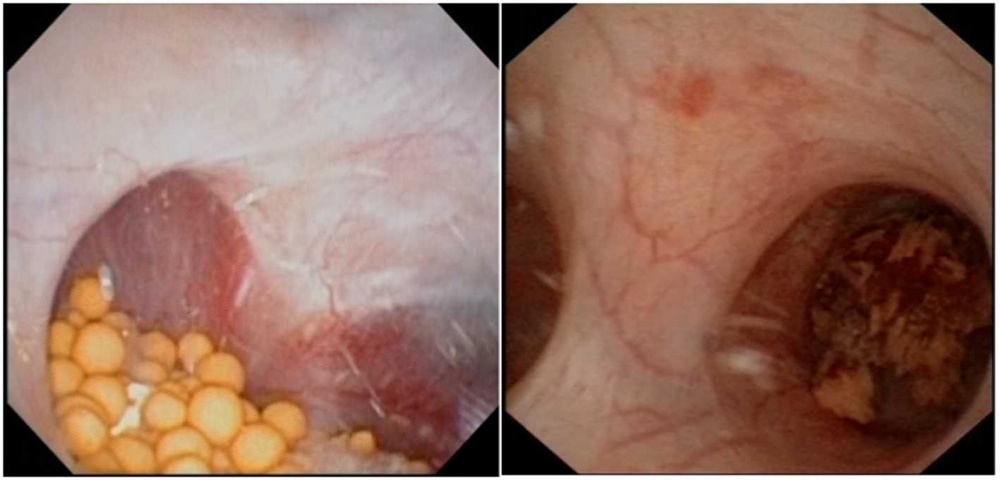

Flexible URS

Kelchsystem; links Steinbeladung mit multiplen kleinen Konkrementen;

rechts Steinbeladung mit einem großen Konkrement

Es handelt sich hierbei um ein flexibles Endoskop (Abbildung 4), mit dem Harnsteine im gesamten Nierenbeckenkelchsystem geborgen werden können (Abbildung 5). Auch hier wird das Bild mittels integrierter Kamera auf eine Videoeinheit übertragen. Um den intrarenalen Druck und die Gefahr der Harnleiterverletzung während der Operation möglichst gering zu halten, empfiehlt es sich, Harnleiterschleusen zu benutzen. Hierdurch wird die Sicht verbessert und der Zugang zum Stein erleichtert [16, 11]. Auch hier stehen